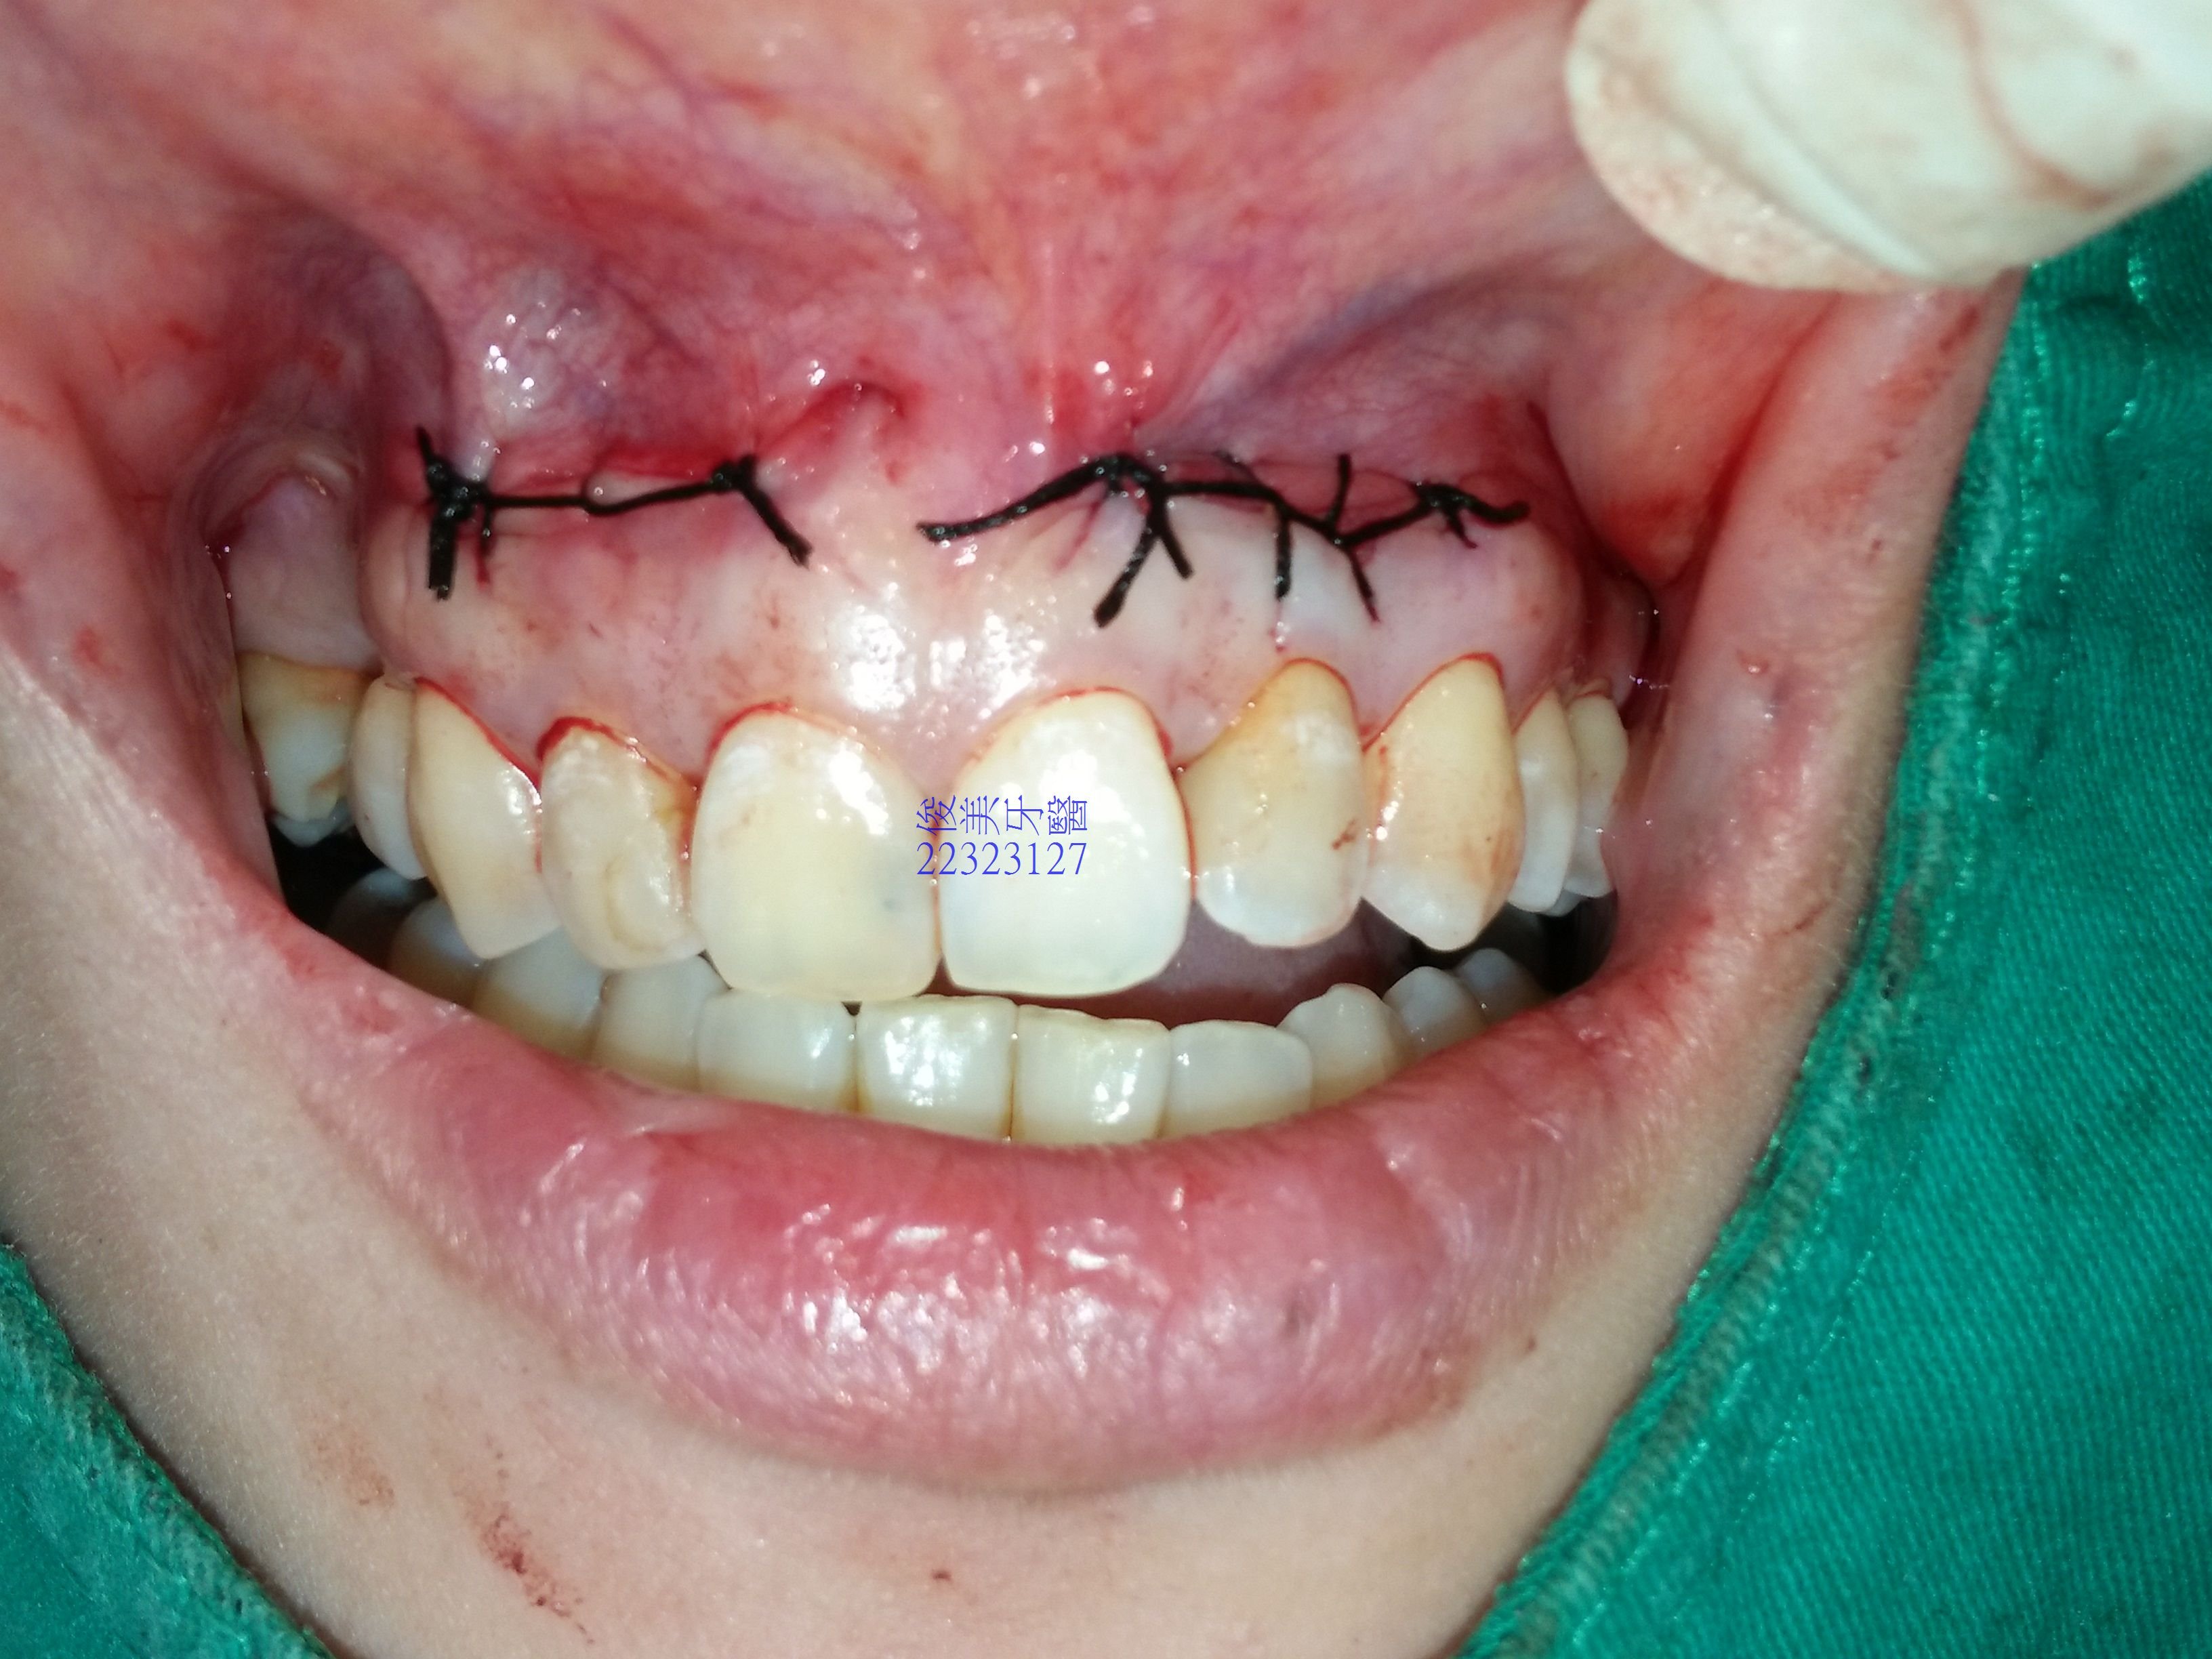

兩邊手術皆圓滿結束。

縫合完成後傷口。

不影響吃東西,但交代患者3-6個月內少用前牙咬東西,讓骨頭癒合的更好。